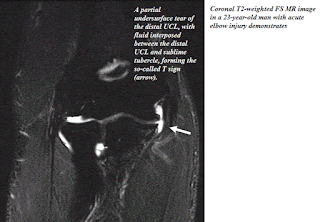

4-1-6-MRI Elbow.